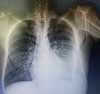

Homens, 30a, tosse produtiva há 5 dias. Qual diagnóstico ?

Pneumonia em lobo inferior direito